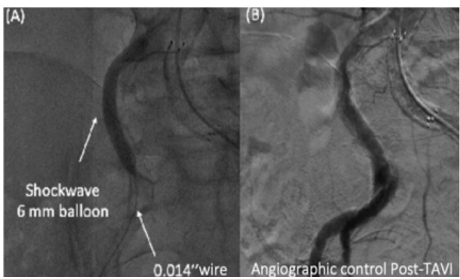

After access puncture and wiring of the operative access with a 0.035-inch wire, PTA was initially attempted at the tightest sites in all cases with non-compliant balloons; however, successful valve advancement was not achieved. Therefore, additional dilatations with the IVL balloon were performed using the Shockwave Peripheral IVL catheter (Shockwave Medical). IVL therapy was delivered in 30 pulses per cycle. Each cycle could be repeated, as needed, until satisfactory luminal diameter gain was obtained and either the valve or the sheath could gain the abdominal aorta. Additional PTA with a non-compliant balloon was performed, as needed, to further increase luminal gain following calcium fracture. Figure 3 provides a step-by-step description of the IVL technique.

(A) The IVL is shown on the left common iliac artery. Fluoroscopy documents IVL balloon expansion. (B) Iliac angiography shows good IVL results and absence of complications. PTA = percutaneous transluminal angioplasty; TAVI = trans-catheter aortic valve implantation.